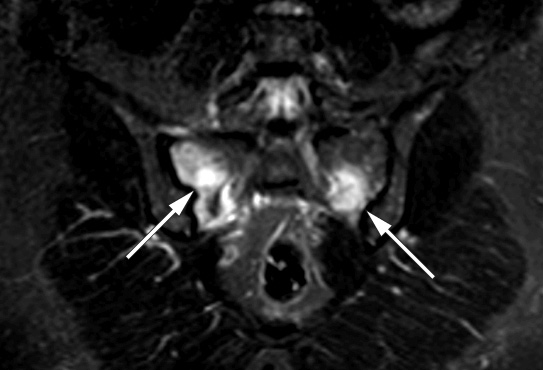

The woman then gradually developed pain extending from the lower back to both gluteal regions. Blood tests revealed normal calcium, low phosphate and elevated ALP levels, PTH in the upper normal range, normal 25-OH vitamin D and 1,25-(OH)2 vitamin D values. MRI scans (STIR sequence) detected high signal changes in both sacral wings and later also on the ileal side, indicating substantial bone oedema (left image). There were radiolucent lines in the sacral wings which raised suspicion of bilateral insufficiency fractures. Full body scintigraphy showed increased uptake in the anterior section of the frontal bone on both sides of the midline, in several ribs, both sacroiliac joints and proximally in the left tibia.

Treatment consists of discontinuing iron saccharide supplements and optionally administering supplements of phosphate and vitamin D orally (2). Fortunately, the renal tubular dysfunction and osteomalacia appear to be reversible, but serious bone deformations may be permanent. At a check-up five months after termination of all iron supplements, the patient was recovering. MRI showed regression of pathological changes (right image). However, the patient still needs treatment for iron deficiency anaemia and is now receiving a different type of iron supplement intravenously. Her need for transfusion varies somewhat, depending on how often she receives iron.